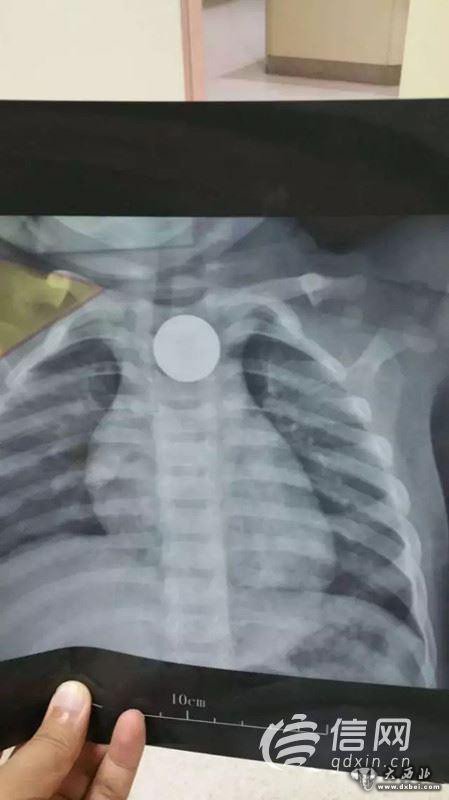

信网7月14日讯 7月12日,一名14个月大的孩子被急匆匆走进青岛市妇女儿童医院,原来5个小时前,孩子误吞下了一枚遥控器的直径为2.2cm的纽扣电池,被确诊为电池卡入食道,青岛市妇女儿童医院将电池取出时,电池表面已经发黑,局部食道黏膜红肿糜烂,且有黑色异物残留,手术医生用蒸馏水反复冲洗半个多小时才将残留的异物冲洗干净。信网了解到,纽扣电池是最危险的消化道异物之一,长时间滞留可逐渐腐蚀食道,甚至会有生命危险。

7月12日晚10:20,一名家长抱着一个14个月大的孩子急匆匆走进青岛市妇女儿童医院耳鼻喉科急诊值班室。“5个小时前孩子误吞下了一枚遥控器的直径为2.2cm的纽扣电池,我们当地医院确诊为电池卡入食道。”

晚上11点10分,患儿被送入手术室,麻醉师和护理人员一边安抚患儿,一边进行麻醉处置和各项护理操作,整个手术间弥漫着紧张的气氛。“因为患儿年龄太小,最小号的食道镜在进入食道时也遇到了很大的阻力,2.2厘米大的异物只能和食道镜一起撤出。”经过手术医生的反复努力,发现电池卡在食道入口下方约2厘米处,电池被顺利取出,此时在场的医护人员松了一口气。